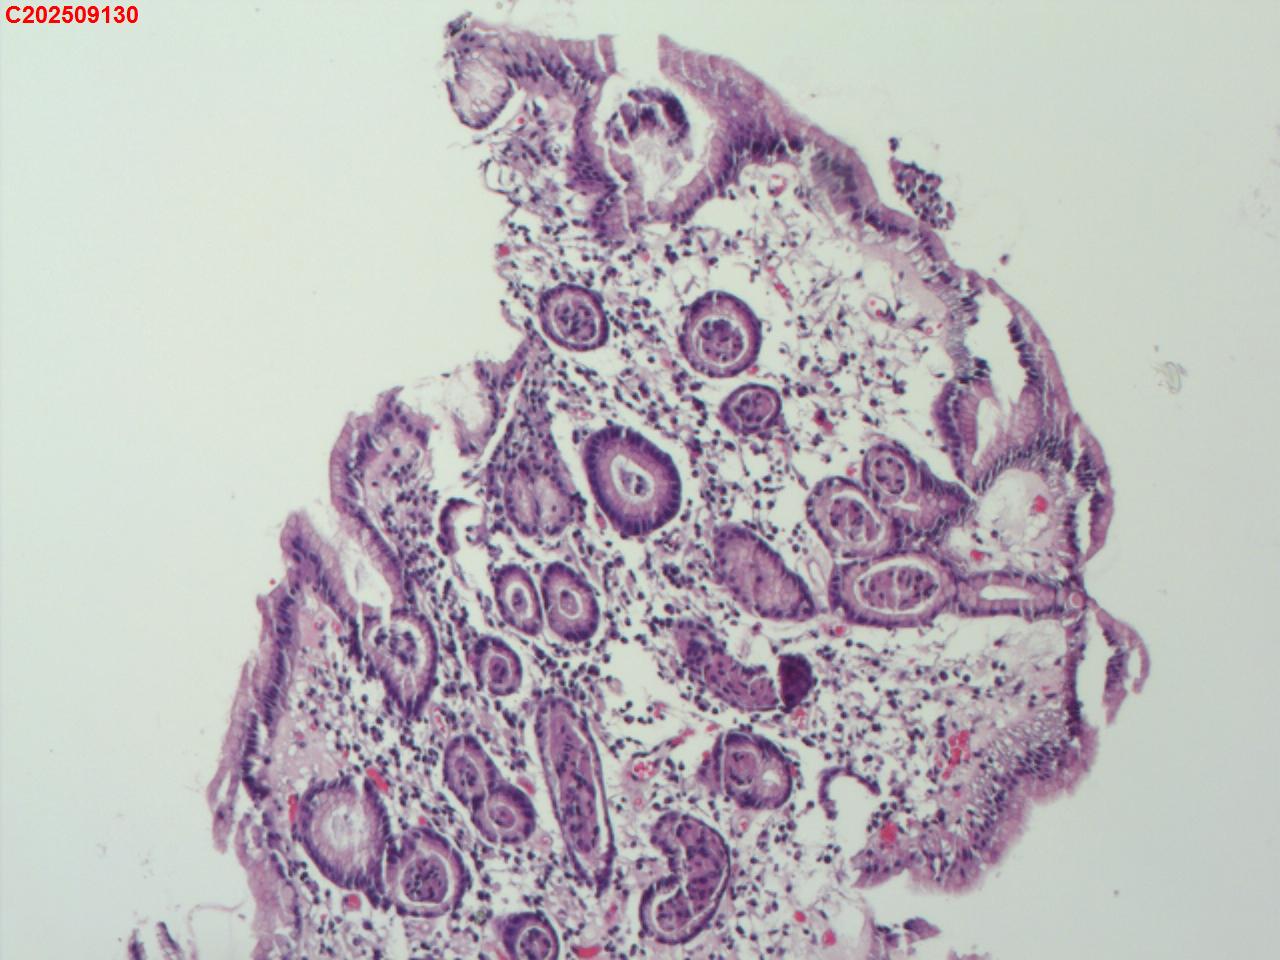

胃体粘膜

性别

女

年龄

76岁

临床诊断

胃息肉

一般病史

体检

标本名称

大体所见

胃体大弯可见一枚直径约2mm息肉样隆起

增生性息肉。